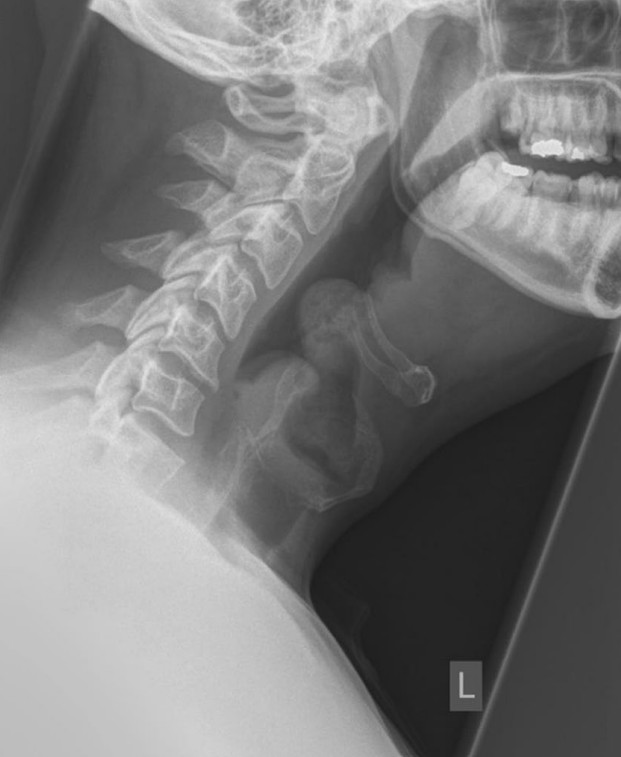

Acquired torticollis

A 6-year-old girl is brought in by her parents with neck pain and stiffness. She is unable to straighten her …